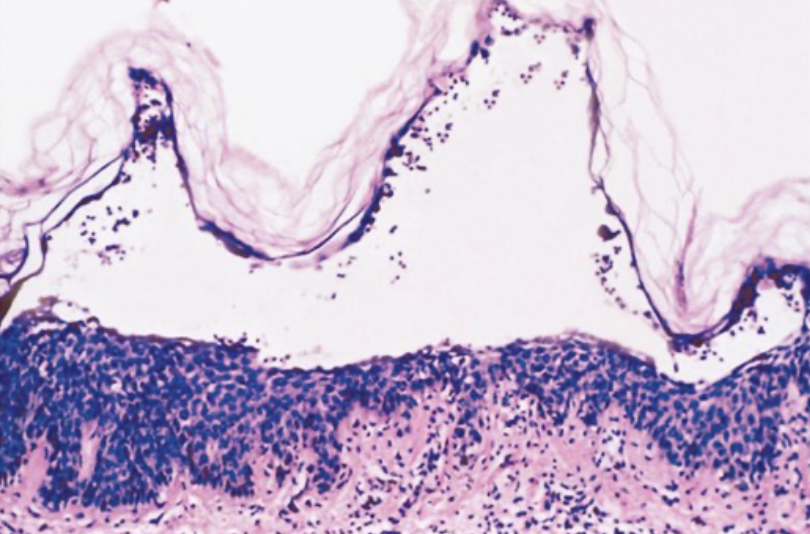

ACANTOLISIS INTRAEPIDERMICA

PV ES SUPRABASAL, SOLO 1 LINEA DE QUERATINOCITOS

EN FIOLACEO SE VE MAS DE 1 LINEA DE QUERATINOCITOS